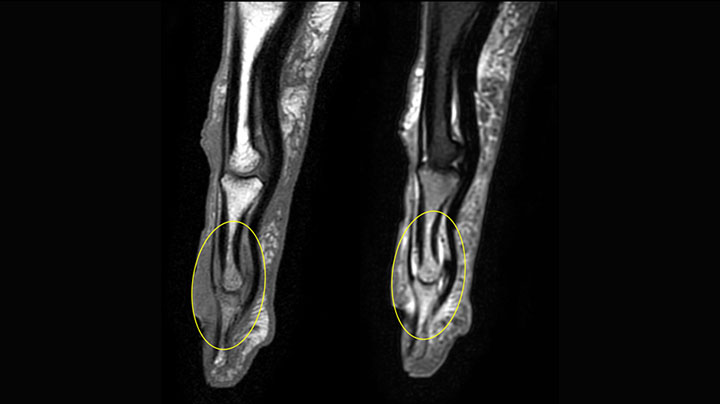

MRI of the finger with high SNR and good resolution in a 10 cm field of view on Prodiva 1.5T. The diagnosis in this 63-year-old patient is bone elasmanosis.